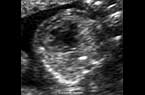

Grossesse débutante intra-utérine de 4SA Grossesse débutante intra-utérine de 4SA Grossesse débutante intra-utérine de 4SA